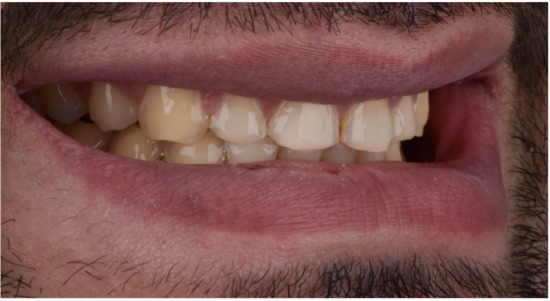

2. Clinical Report

2.1. Planning Phase